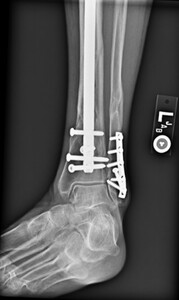

time of transition from a flexed position to semi extended position. This was not dictated by fracture location or type. It is current practice to use the semi extended position in the majority of cases currently. Multiple bone reduction forceps were used to obtain and maintain this reduction. If the fracture was transverse in nature then small drill holes were placed on either side of the fracture and then reduction forceps were used to reduce the fracture. Provisional plates were not used in this series. Please see figures below for radiographs of a representative case. All portions of the case were completed by the treating surgeon as there are few operative assistants available in this clinical setting. The intramedullary nail was then placed though an extraarticular lateral parapatellar approach in a semi extended position (Kubiak, Widmer, and Horwitz 2010) or through a medial parapatellar approach with the knee flexed over a radiolucent triangle. If the fibula was fractured, it was not routinely operatively repaired unless the ankle was found to be unstable. If the ankle was unstable, then the fibula was treated through a separate incision with a plate and screw construct. All wounds were closed in layers with absorbable suture for the fascial layers. Either 0 or 2.0 Vicryl was used in interrupted figure of 8 fashion. All skin incisions were approximated with 3.0 nylon in modified Allgower-Donati fashion (Shannon et al. 2017). All patients were placed into well-padded short leg plaster splint with the foot in neutral dorsiflexion and made non weight bearing until wounds were healed and sutures were removed. At that point all patient were made weight bearing as tolerated on the effected extremity with or without a cast boot as the patient desired.

Out of the 32 patients, zero patients required reoperation for deep infection. 2 of 32 required a short course of oral antibiotics for reported cellulitis after these patients visited outside urgent cares. On follow up exams with the treating surgeon in these 2 cases no sign of active infection was found on exam and antibiotics were discontinued. One patient did use tobacco and also had a history for alcohol abuse. The other patient had diabetes mellitus and atrial fibrillation. Both of these were closed injuries as well. In both cases, wounds healed uneventfully without any further procedures or treatment required. Four patients required reoperation for painful hardware, in all cases distal bolt or associated plates for fibula fixation were removed. One patient had one prominent locking bolt removed in the office under local anesthesia. No reoperations were needed for nonunion. All fractures were found to be healed radiographically at time of final follow up for each patient.